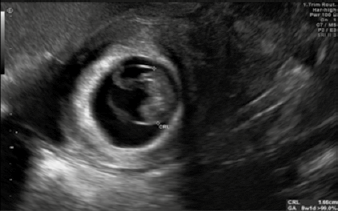

La subunidad β de la gonadotropina coriónica humana cualitativa se reportó positiva. El ultrasonido abdominal y endovaginal (Figuras 1 y 2) reportaron una gestación de 8.1 semanas, con saco gestacional en la cavidad endometrial, con feto único vivo de longitud cráneo-caudal de 1.66 cm. En el anexo izquierdo y el fondo de saco se observó una imagen heterogénea de bordes difusos de 10.6 x 6.6 x 9.5 cm, compatible con plastrón y 356 cc de líquido libre hipoecoico.

Figura 1 Corte sagital del útero en donde se observa un embarazo intrauterino, con una longitud craneocaudal de 166 mm (8.1 SDG)